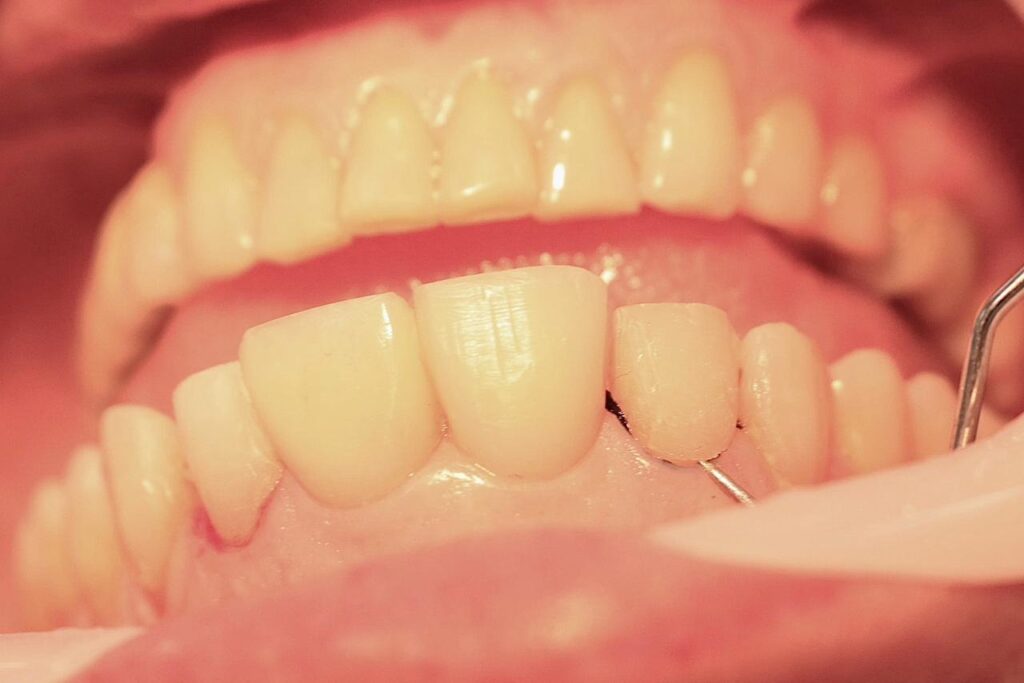

A coleta de dados foi iniciada com a realização de uma consulta inicial, na qual foi conduzida uma anamnese detalhada para levantamento do histórico médico e odontológico do paciente, bem como de suas principais queixas e expectativas em relação ao tratamento estético proposto. Em seguida, foi realizado um exame clínico minucioso com o objetivo de avaliar as facetas previamente instaladas, observando critérios como adaptação marginal, integridade do material restaurador e condições periodontais adjacentes. A saúde bucal geral do paciente também foi analisada nesta etapa, no aspecto inicial foi observado o acúmulo de biofilme causado pela má adaptação cervical, retração gengival, trincas e fraturas derivadas da oclusão desbalanceada, conforme apresenta a figura 1,2,3 e 4.

Figura 4: Vista frontal com ênfase na região cervical do elemento 12